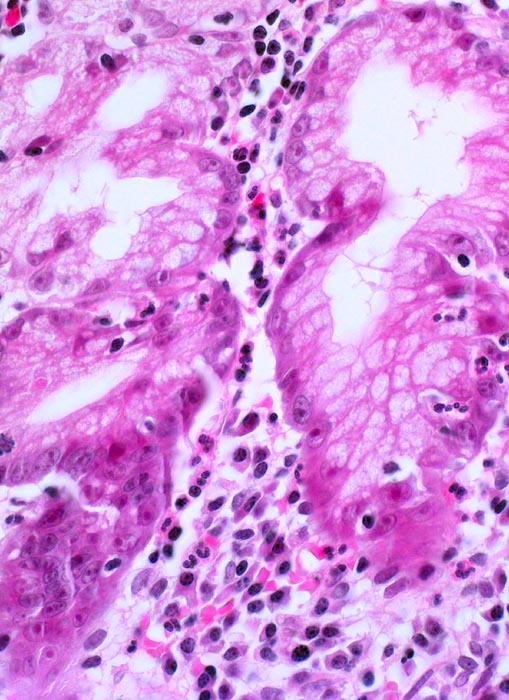

Chronische Helicobactergastritis

Entzündung infektiös

Magenantrum

Die Lamina propria enthält Plasmazellen, Lymphozyten, neutrophile und eosinophile Granulozyten. Einzelne neutrophile Granulozyten infiltrieren das Drüsenepithel. Als Reaktion auf die Entzündung zeigen die Drüsenepithelzellen Atypien (vergrösserte blasige Kerne mit grossen Nukleolen).

Asylsuchender aus dem Balkan mit chronischen Oberbauchbeschwerden.

400